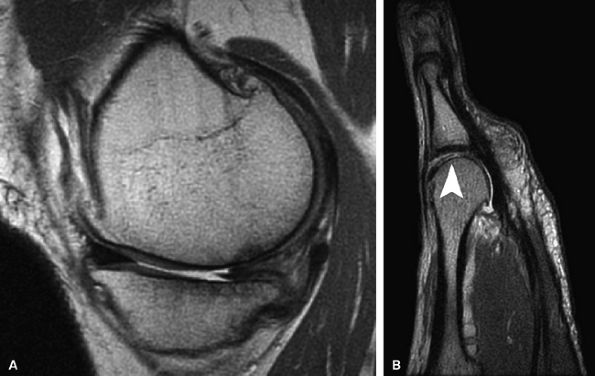

FIGURE 7.9 ● Fast spin-echo MR images obtained in a 0.7-Tesla open unit. (A) Sagittal image of the knee in a 40-year-old patient demonstrates a chronic tear of the posterior horn of the medial meniscus, full-thickness cartilage loss, and sclerotic changes in the subchondral bone over the medial compartment. (B) Sagittal image of the forefoot in a 48-year-old patient demonstrates active cartilage delamination (arrowhead) and flap formation over the head of the second metatarsal.